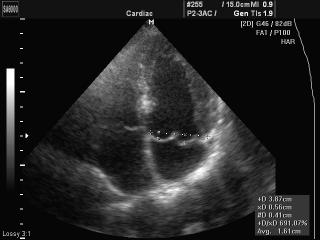

- Пакет кардиологических исследований:

- в 2D-режиме рассчитываются значения таких параметров, как объем по методу Симпсона (Simpson), объем по площади и длине, двумерные характериcтики (например, фракция выброса левого желудочка) и масса левого желудочка;

- в M-режиме вычисляются значения параметров для левого желудочка, аорты и левого предсердия, митрального клапана, а также частота сердечных сокращений. - Пакет расчетов параметров сосудов: вычисления объемного кровотока, процента стеноза, индекса сопротивления (RI), пульсационного индекса (PI) и др.

Фазированный датчик P 2-5AC/15

Кардиология и транскраниальные исследования у взрослых.

Фазированный датчик P 2-5AC/19

Фазированный датчик P 3-7AC/10

Кардиология и транскраниальные исследования у детей.